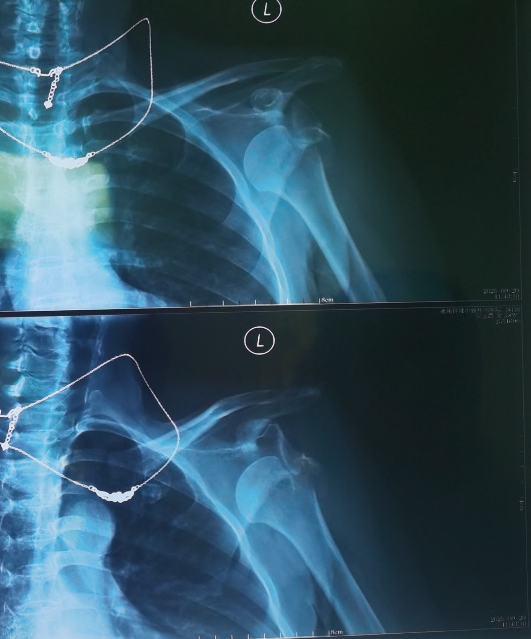

患者术前三维重建检查可见肱骨大结节粉碎性骨折